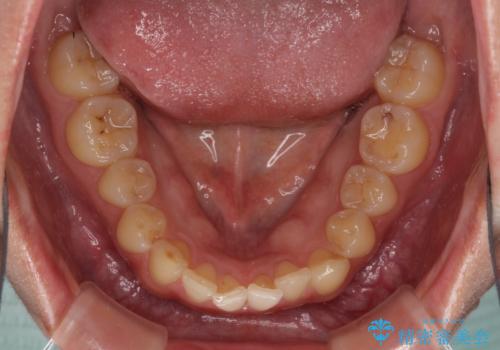

- 食いしばりが気になっていたとのことで来院された患者様です。

当初は睡眠時のマウスピースのみの製作をご希望でしたが、矯正治療の提案をしたところ、インビザラインにて矯正治療を行うこととなりました。

矯正治療中に食いしばりがより強くなることがあるため、半年に1回のペースでボツリヌストキシンによる咬合力緩和を並行して行うこととしました。

咬合力の緩和と食いしばりがちな咬み合わせが改善され、顎の負担が大幅に軽減されました。